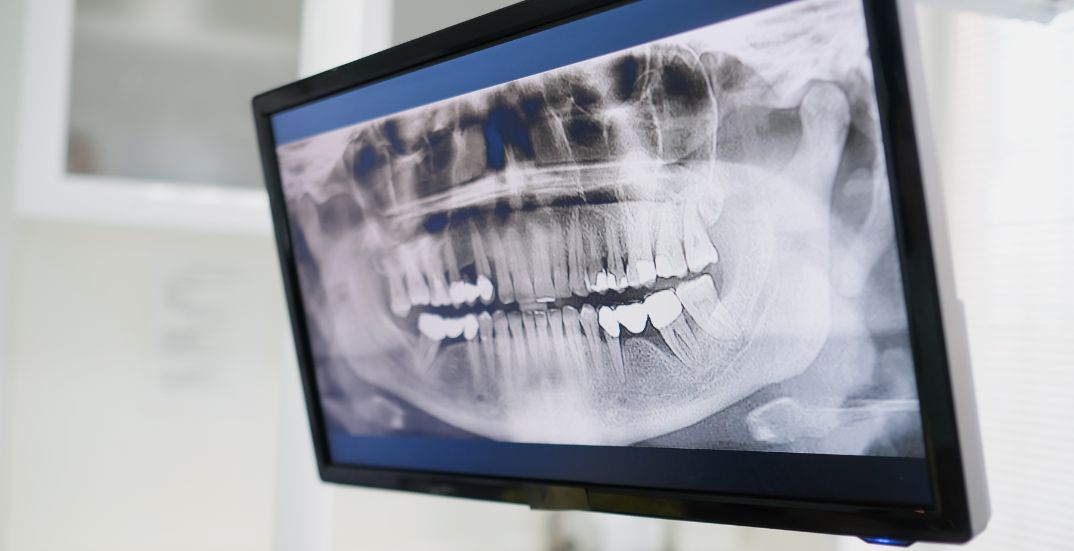

Pain isn’t the only sign of infection. Dental X-rays often reveal damage even when you feel fine. Ignoring it can lead to serious issues like abscesses or tooth loss.

The process begins with an X-ray to assess the extent of infection. The area is numbed using a local anesthetic. A small hole is made to access the pulp, which is then carefully removed. The canals are cleaned, shaped, and disinfected before being sealed. In many cases, a crown is placed later to protect the tooth.

It’s essential to consult a qualified dental professional who can diagnose the issue using clinical examination and imaging tools, such as X-rays.